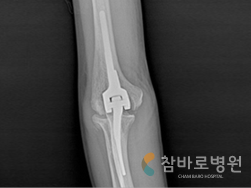

2. 팔꿈치 인공 관절 수술

· 심한 팔꿈치 관절염으로 움직일 수 없고

신경이 눌리는 상태

· 인공관절 치환술과 신경 전위술로

일상 생활이 가능한 상태